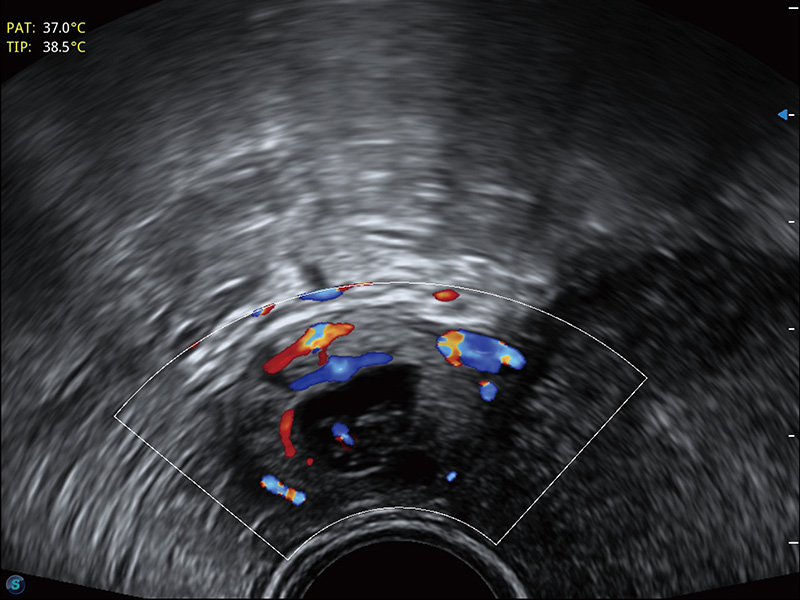

超声引导下胚胎移植

宫外孕血流